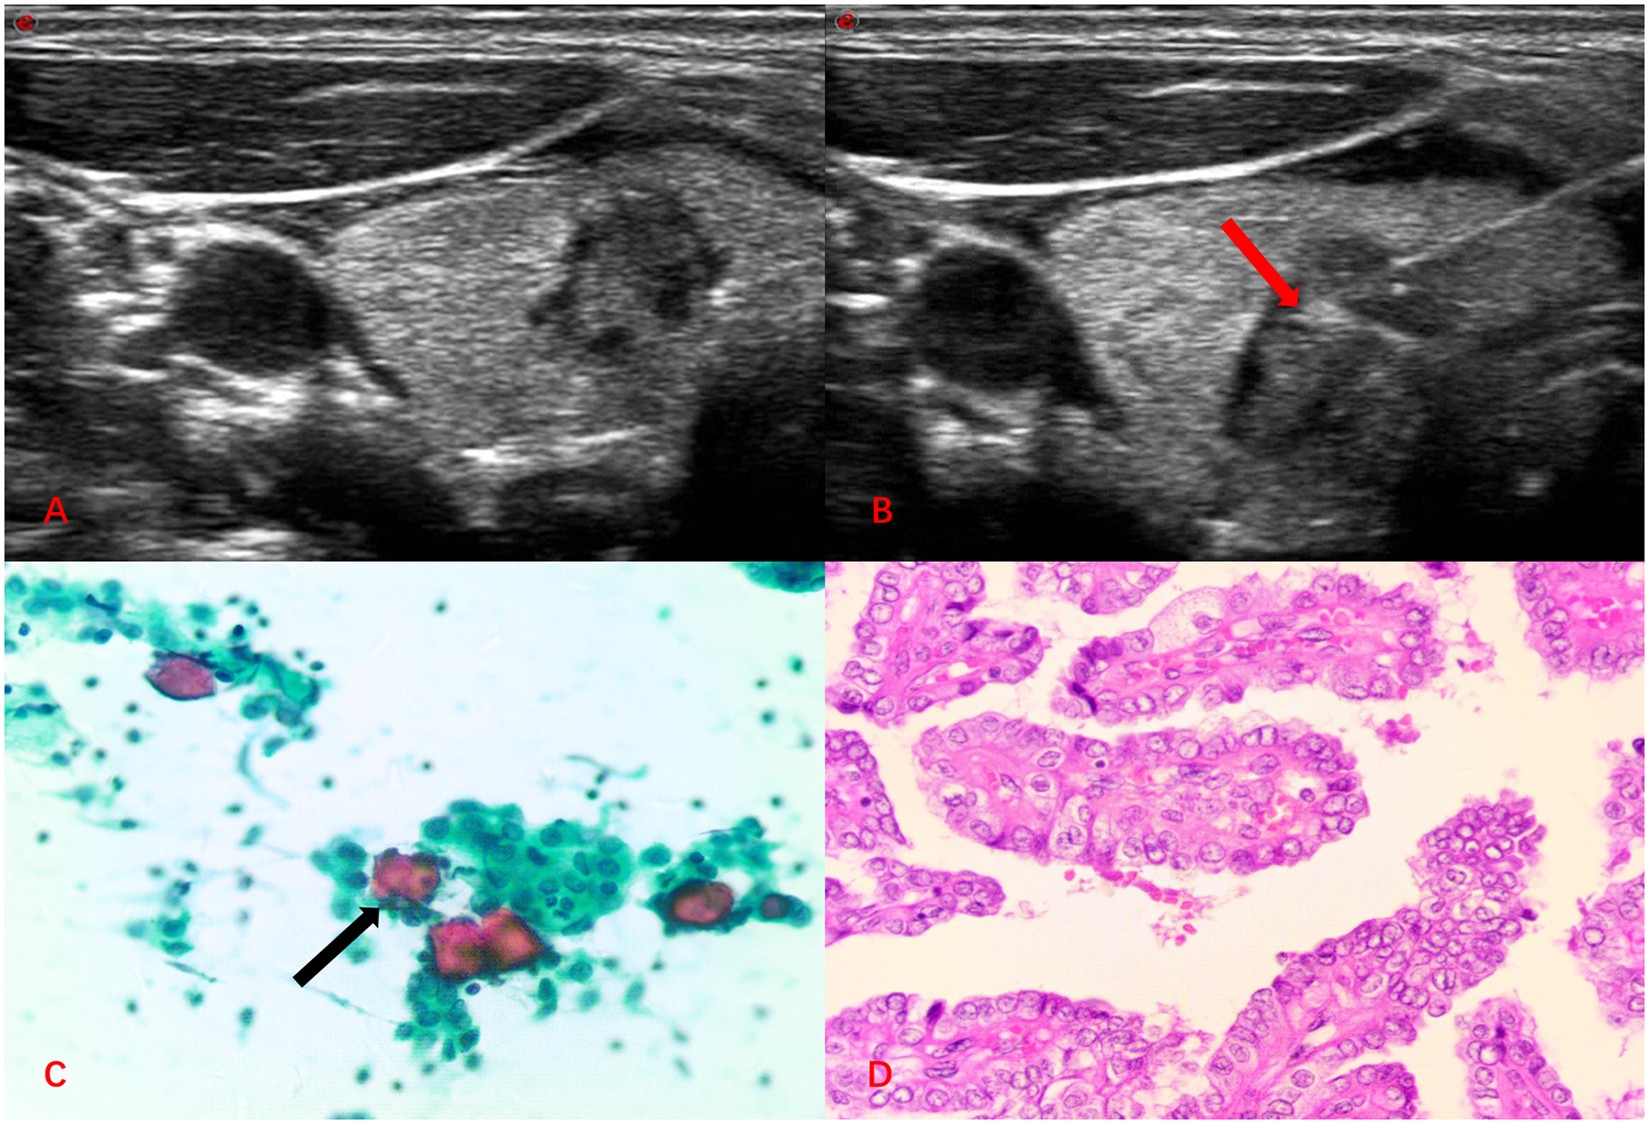

Figure 3

Image of a 39-year-old woman with a thyroid nodule in the left lobe. (A) The two-dimensional ultrasound showed a lesion with irregular margins in the left lobe. (B) On FNA, the needle tip passed through the center of the nodule (Red arrow). (C) FNAC smear showing features of malignant thyroid nodule, for example, pasmmoma body (Black arrow, Papanicolaou, × 400). (D) Histopathology showing features of papillary carcinoma (Hematoxylin and eosin, × 400).